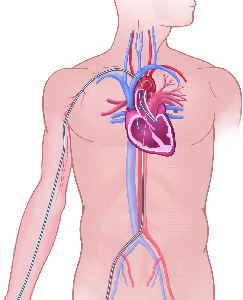

Detailreiche Fotografien aus der medizinischen Praxis ergänzen die Texte; moderne, genaue,

wissenschaftliche Zeichnungen geben Einblick in die Anatomie und die Funktion der Lunge und

anderer Organe.